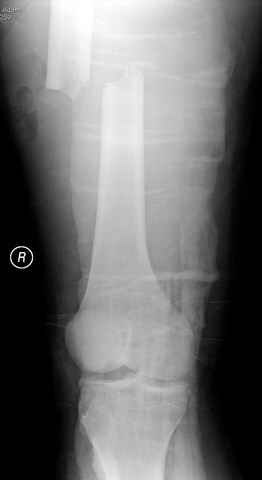

03.14.2005

больному 42, автоавария, политравма, открытая черепномозговая травма, безсознании, открытый перелом бедра, размозжение мягких тканей, дефект кожи на передней поверхности бедра около 13 см2 от ожога, компартмент синдром.

По поводу открытого перелома больной ургентно взят на ретроградное интрамедулярное штифтование, после рутинного дебрайдмента и фасциотомии на бедре и на голени.

перелом бедра